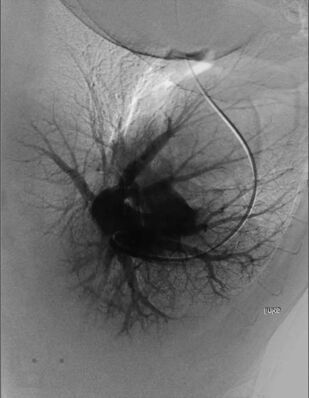

В четвертом томе четырехтомного руководства по кардиологии описываются этиология, патогенез, диагностика, клиническое течение и лечение сердечно-сосудистых заболеваний, в частности сердечной недостаточности, миокардитов, кардиомиопатий, легочной артериальной гипертензии, приобретенных пороков сердца, инфекционного эндокардита, перикардитов, опухолей и травм сердца, болезней сосудов. Приводятся также сведения об основных классах лекарственных препаратов, применяемых для лечения сердечно-сосудистых заболеваний. Руководство предназначено для кардиологов, терапевтов, врачей общей практики (семейных врачей), кардиохирургов, специалистов по рентгеноэндоваскулярной диагностике и лечению, врачей других специальностей, принимающих участие в обследовании и лечении больных с заболеваниями сердечно-сосудистой системы, и студентов высших медицинских учебных заведений.